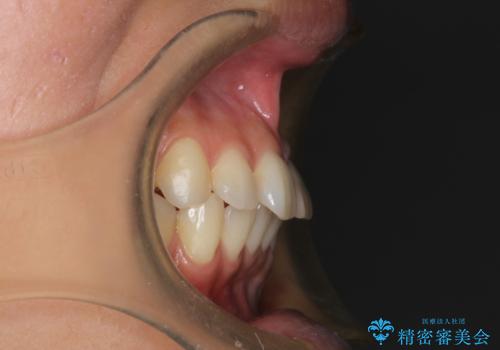

上下裏側矯正 フルリンガルによる上下前歯前突の歯列矯正

- 20代女性

- 舌側矯正装置

- 口元を改善するため、上下左右4本の第1小臼歯を抜歯し、前歯を後方に牽引する計画としました。

今回は歯列に大きなガタつきはないため、抜歯してできたスペースを最大限閉鎖しなければなりません。牽引による前歯の倒れ込みを防ぐため、ループを組み込んだワイヤーに曲げを付与し、牽引と倒れ込みの予防を同時に行うことができます。